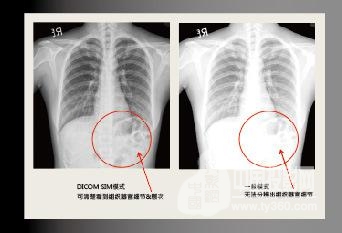

支持DICOM.SIM医疗设备模拟显示模式

DICOM.SIM 显示模式能够使投影机模拟医疗设备的灰度/Gumma性能来显示图像,相对没有没有DICOM模式的投影机,可以更精准地表现灰阶图像,且清楚地传达医疗讯息,有助于诊断&治疗细节讨论。 注:此模式仅用于教育培训或会议讨论,医疗诊断禁止使用!